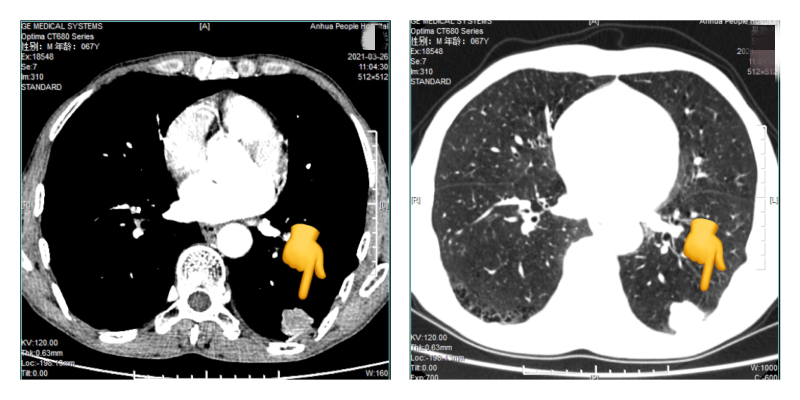

患者吴**,男, 67岁。因“发现左下肺结节15天”于 2021年04月01日入院。我院3月26日胸部CT平扫三维成像加增强:1.左肺下叶后基底段占位性病变,考虑周围型肺癌可能性大。我院3月26日肺穿刺取组织送检病理结果示:恶性肿瘤。